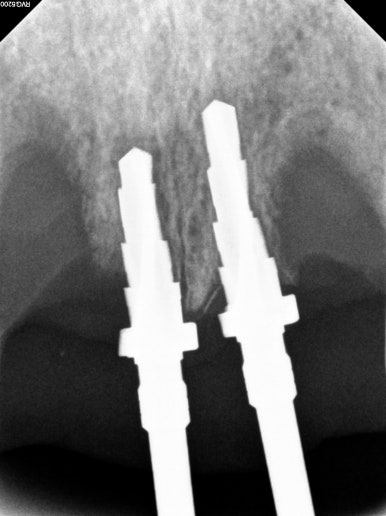

남은뼈가 굉장히 적었기 때문에, 치과용 치근단방사선사진을 촬영해가며 그 위치를 설정하였습니다.

모자이크를 하였지만, 얼핏 보이는 실루엣으로 얼마나 많은 뼈가 사라졌는지 가늠하실 수 있으실거에요.